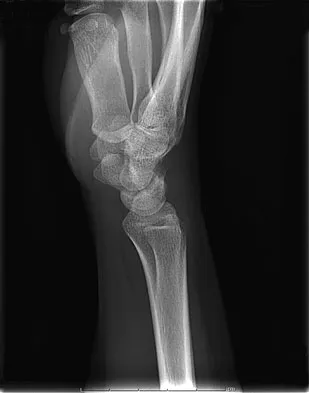

A 19-year-old woman fell onto her nondominant hand 6 weeks ago. Radiographs are shown in Figures 37a and 37b. A decision has been made to treat this fracture surgically. What is the best approach to treat this fracture?

Explanation

Displaced fractures of the scaphoid are best treated with compression screw fixation. Proximal third fractures (as in this patient) are optimally approached via a dorsal approach to ensure proper reduction and compression. Fractures of the scaphoid waist can be approached either by a volar or a dorsal approach. Kirschner wire fixation is limited to proximal pole fractures that are too small to accommodate the trailing head of a compression screw. Retting ME, Raskin KB: Retrograde compression screw fixation of acute proximal pole fractures. J Hand Surg Am 1999;24:1206-1210.